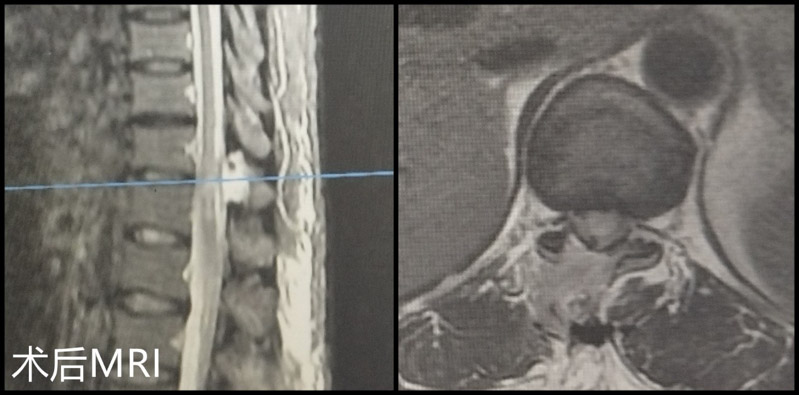

術(shù)后患者下肢雙下肢疼痛、麻木的明顯緩解,復(fù)查胸椎CT和MRI,可見手術(shù)已達(dá)到了預(yù)期的減壓效果。顏阿姨非常滿意,對(duì)醫(yī)護(hù)人員表達(dá)了衷心的感謝,目前已康復(fù)出院。